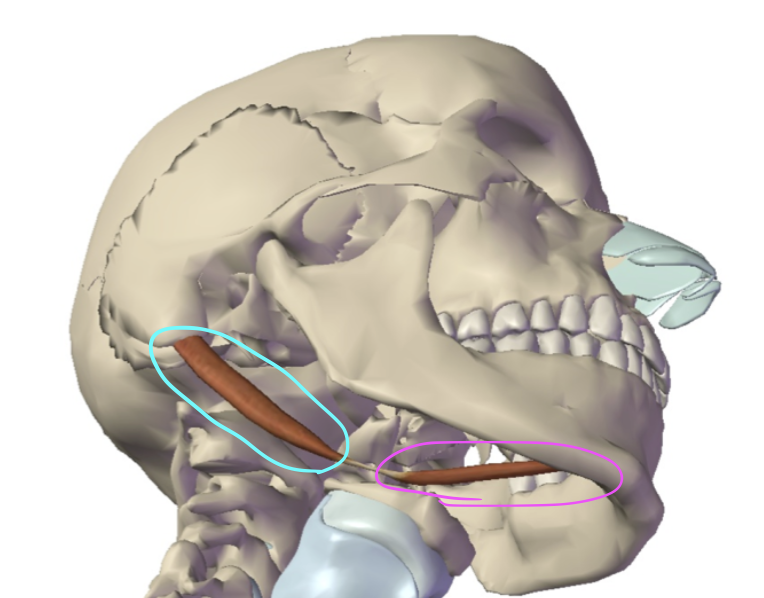

What is this muscle circled in pink?

Anterior digastric (hyoid up and forward)

What is this muscle circled in teal?

Posterior digastric (hyoid up and back)